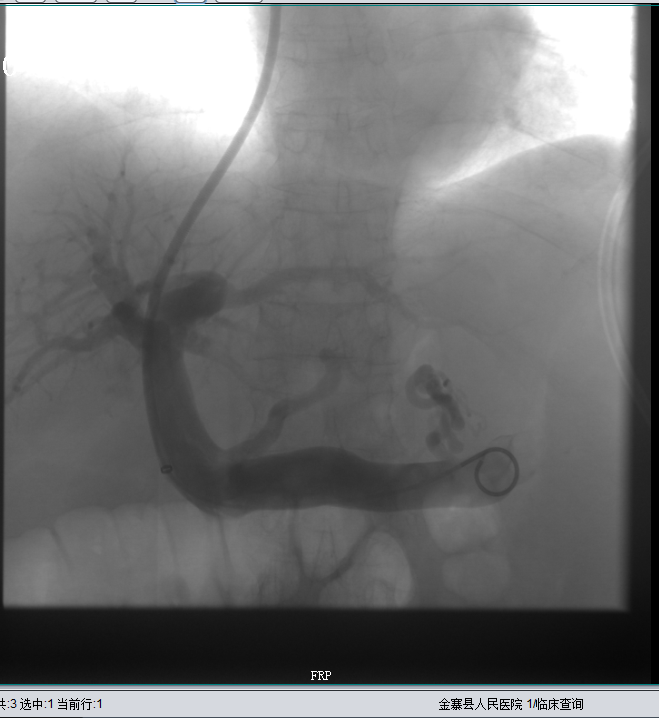

胃冠状静脉栓塞后,未见血流

2020年1月7日再次出现腹胀伴下肢浮肿等症,至我院外周介入科就诊。上腹部增强CT示:1、肝硬化;2、腹水;3、门静脉高压;4、食管下段静脉曲张;5、脾脏增大;6、脾脏局限性梗死。入院时腹围约51cm,积极完善相关辅助检查,于1月10日行“经颈内静脉肝内门体分流术+胃冠状静脉栓塞术”,术后患者腹胀症状明显好转,腹围约38cm,术后给予保肝、抗凝等对症治疗。